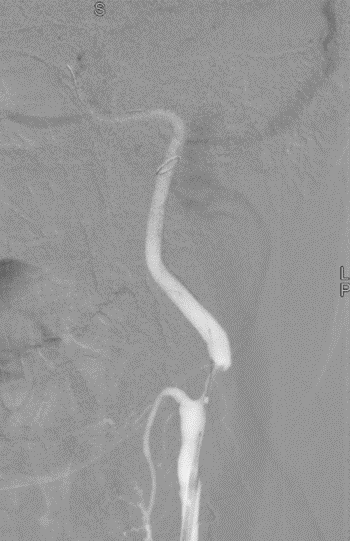

球囊扩张并造影。

波科支架怎么样径技-弓上病例大赏|第205期·放疗后症状性颈动脉狭窄支架置入治疗一例_https://www.jmylbn.com_新闻资讯_第15张

波科支架怎么样径技-弓上病例大赏|第205期·放疗后症状性颈动脉狭窄支架置入治疗一例_https://www.jmylbn.com_新闻资讯_第16张